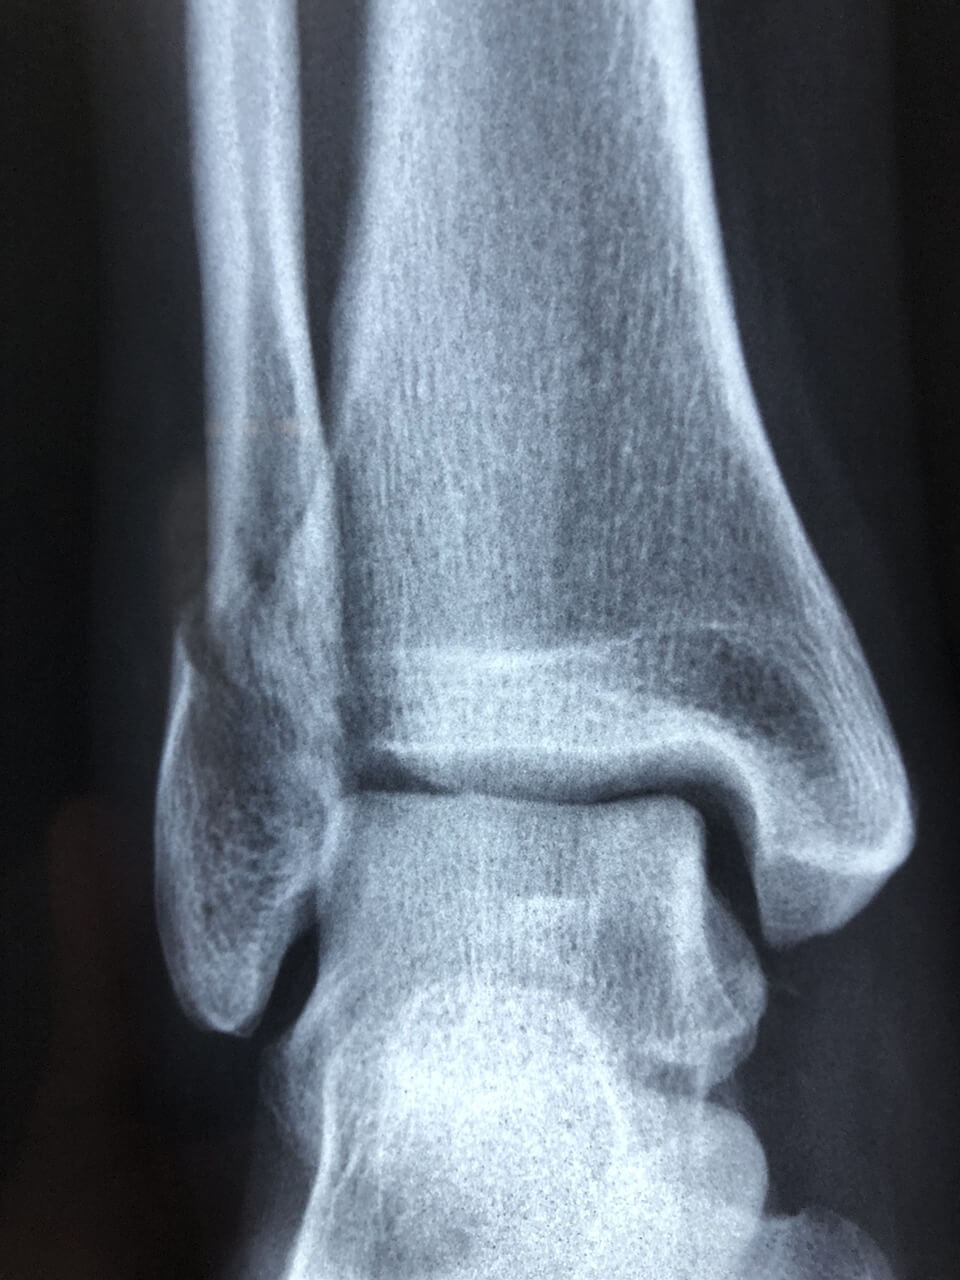

- 수술 고려

3~6개월 표준 재활에도 통증 지속·부분 파열 의심 시 수술적 처치 고려. 이후 단계적 체중부하·관절 가동 범위 복원이 아킬레스건염 예후를 좌우합니다.